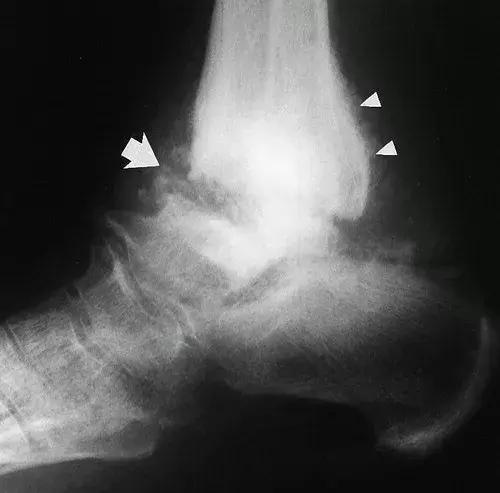

图15:27岁女性糖尿病人,踝关节的神经性骨关节病。侧位X线片显示了大的踝关节积液,其具有碎裂和胫骨关节塌陷(实线箭头)。 存在微血管钙化(空心箭头),表明糖尿病是神经性骨关节病的原因。 虽然不如脚的神经性畸形常见,但糖尿病神经病变患者也会发生神经性踝关节改变。